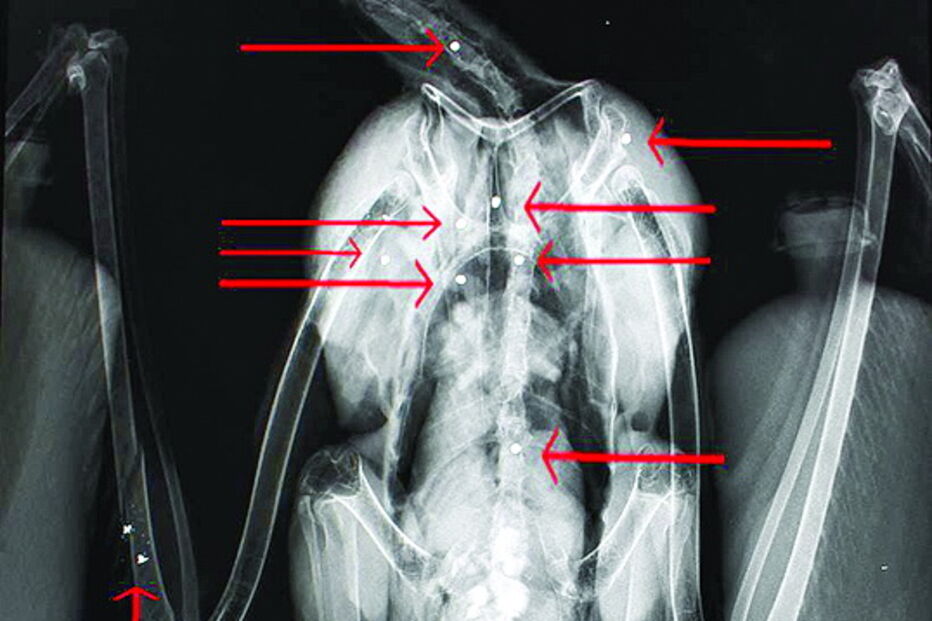

Uma cegonha branca (Ciconia ciconia), com cerca de 4 anos, foi alvejada com 10 chumbos de caçadeira em vários locais do corpo, no passado dia 12 de Abril, no Algarve.

O CM apurou junto da bióloga e coordenadora do (RIAS) Fábia Santos que "quando o animal chegou foi feito imediatamente um exame sistematizado e uma radiografia, onde foi verificado que o animal tinha 10 chumbos de caçadeira, que estava fraturada a asa direita e foi possível verificar a presença de um ovo, que estava afetado parcialmente e foi expulso" pela ave.